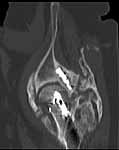

49 year old male, active speedskater, one year after MVC with multiple trauma and mild traumatic brain injury. Pipkin type IV fracture of the left hip. Same day ORIF through KL approach. No heterotopic ossification "prophylaxis". Day 7 wound revision for hematoma. Full weightbearing after 3 months. Full recovery except left hip function due to early severe HO. Function after one year: fixed ankylosis in 40 degrees flexion, 10 degrees exorotation. Patient frequently asks for attempt to improve hip function.

Post Op 1 year - Click to Magnify

Use the CT scan to direct your exposure for excision ... operate wherever the bone is ... sometimes it forms remote from your initial surgery site and demands a separate exposure.

A 3D CT helps define the margins and direct the exposure(s).